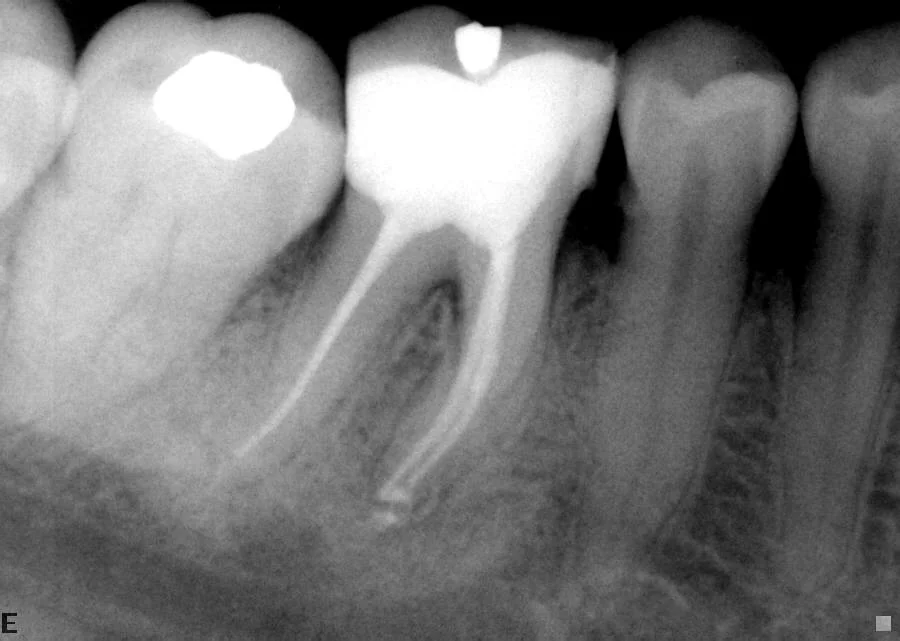

A large filling has killed the nerve in the tooth. Options are root treatment (endodontics) or extraction.

The tooth had an extremely curved root. After endodontics, the tooth does not need to be extracted and is functional.